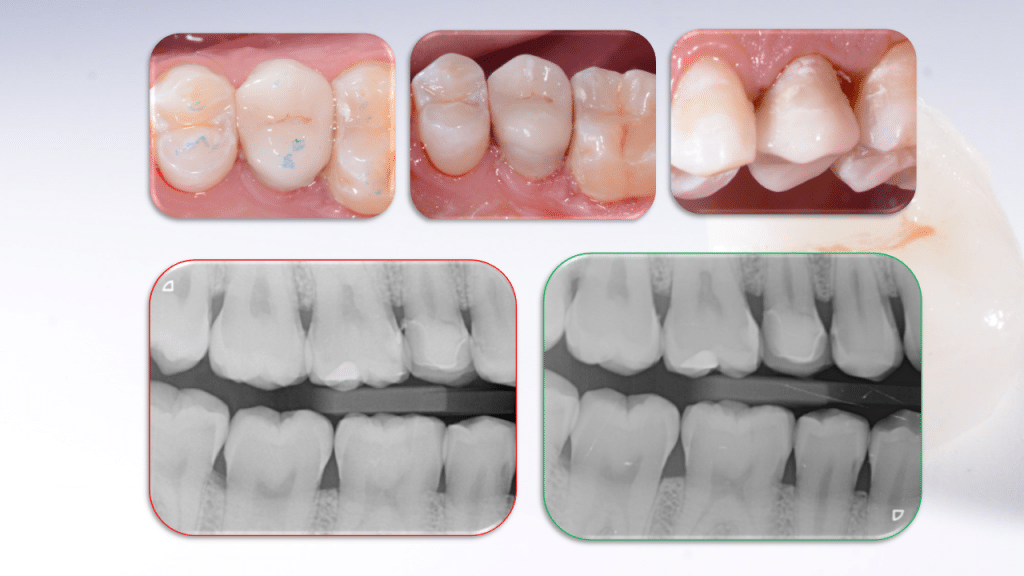

The patient, 23 Y.O. , presented for clinical inspection with asymptomatic distal destructive caries on right second upper premolar.

At the bitewing examination mesial and distal radiotranslucency with intimate pulp contact is noted.

Clinical and radiographic control at three months showed no alterations. The tooth responds normally to vitality tests and the restoration has excellent integration.

Time 0

Excavation of decay exposing pulp

Immediate post op. Always check radiography

3 months control.